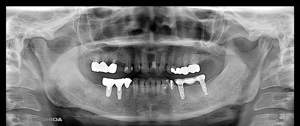

@@R.S‚³‚ñ@56Î —«  ‘åŠw‹³Žö @Žèp“ú@‚Q‚O‚O‚W”N ‚QŒŽ ‚X“úi“yj@㉺Š{  ƒm[ƒxƒ‹ƒKƒCƒhŽg—p@Ö¬“à’ÁÖ@•¹—p@@@

@@@@@ãŠ{  All on ‚U@‘¦Žž‰Ád@@

@@@@@@@@@@@@@ Rpl Tapered Rp  ‚P‚O mm(‚U–{)

@@@@@‰ºŠ{¶‰E@‘¦Žž‰Ád@ ‚R Unit Bridge@

@@@@@@@@@@@ @Rpl Tapered Rp  ‚P‚O mm(‚S–{)@@–ƒWƒ‹ƒRƒjƒAƒNƒ‰ƒEƒ“‚ÅÅI•â’Ô